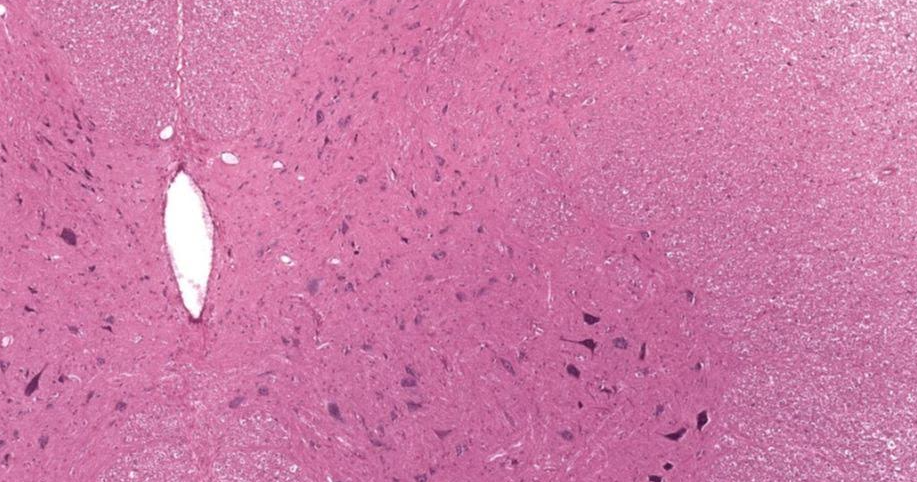

Medula espinhal (1: substância cinzenta; 2: substância branca)

Medula espinhal